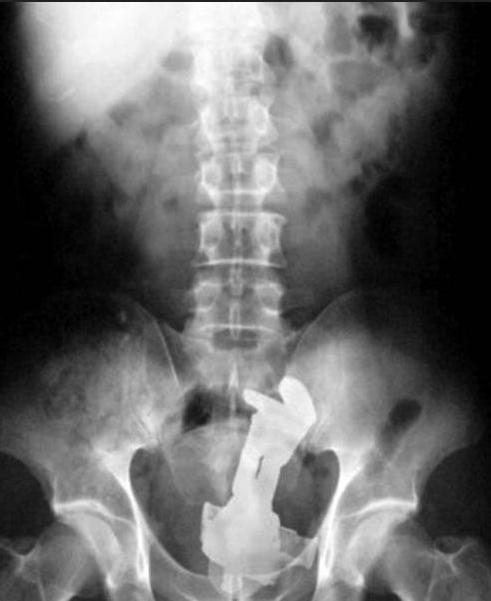

・股間以外のマグナム